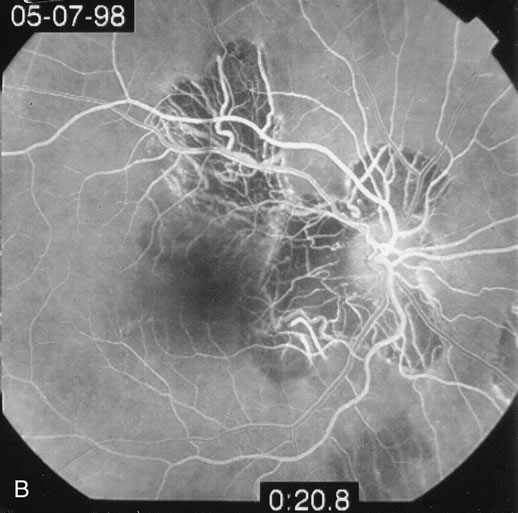

Some patients present with subretinal bands that extend between chorioretinal scars. In addition there may be initial active yellow choroidal lesions that subsequently become atrophic. Vitreous cells are usually present although they may be few and difficult to detect. Visual acuity loss in these cases may be due to active choroidal neovascularization, subretinal bands under the fovea, or from cystoid macular edema. The vast majority of affected patients are women with a mean age of 27 years and both eyes are usually involved. The affected individuals tend to be myopic.49 The age range is from 6 years to 76 years and there is no racial predilection.40 Whether it is a separate disease or a more severe form of multifocal choroiditis is controversial (Figs. 10 and 11). Aggressive therapy is warranted because it has a poorer prognosis than most cases of multifocal choroiditis. This syndrome has been called either diffuse subretinal fibrosis or progressive subretinal fibrosis syndrome.

Fig. 10. A. Fundus photograph showing the subretinal fibrosis extending from the disc to the periphery in a case of diffuse subretinal fibrosis. B. Fundus photograph showing the marked fibrosis in the midperiphery. C. Multifocal choroiditis type lesions noted in the inferior retina.